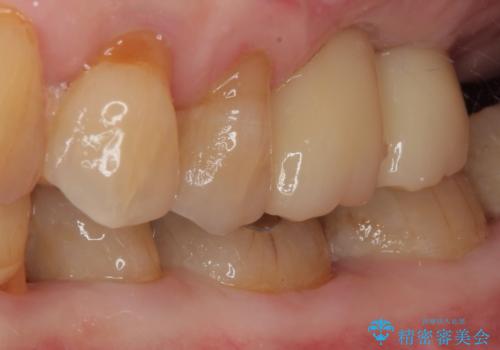

骨量の少ない上顎大臼歯 骨補填材を用いない短期間インプラント治療

元々の骨量が少なく、通常よりは待機期間が長くなりますが、数ヶ月程度で補綴治療まで行うことができるため、こちらの手法でインプラント補綴治療を行うこととしました。

インプラントが待機期間に脱落することがありますが、一切のトラブルなく、最短期間で無事に治療を終えることができました。